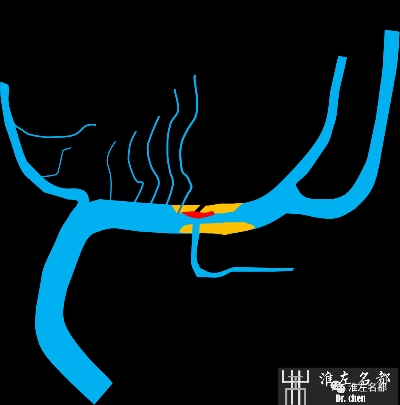

术中游离颞浅动脉,暴露大脑中动脉M4段,行STA-MCA吻合术。